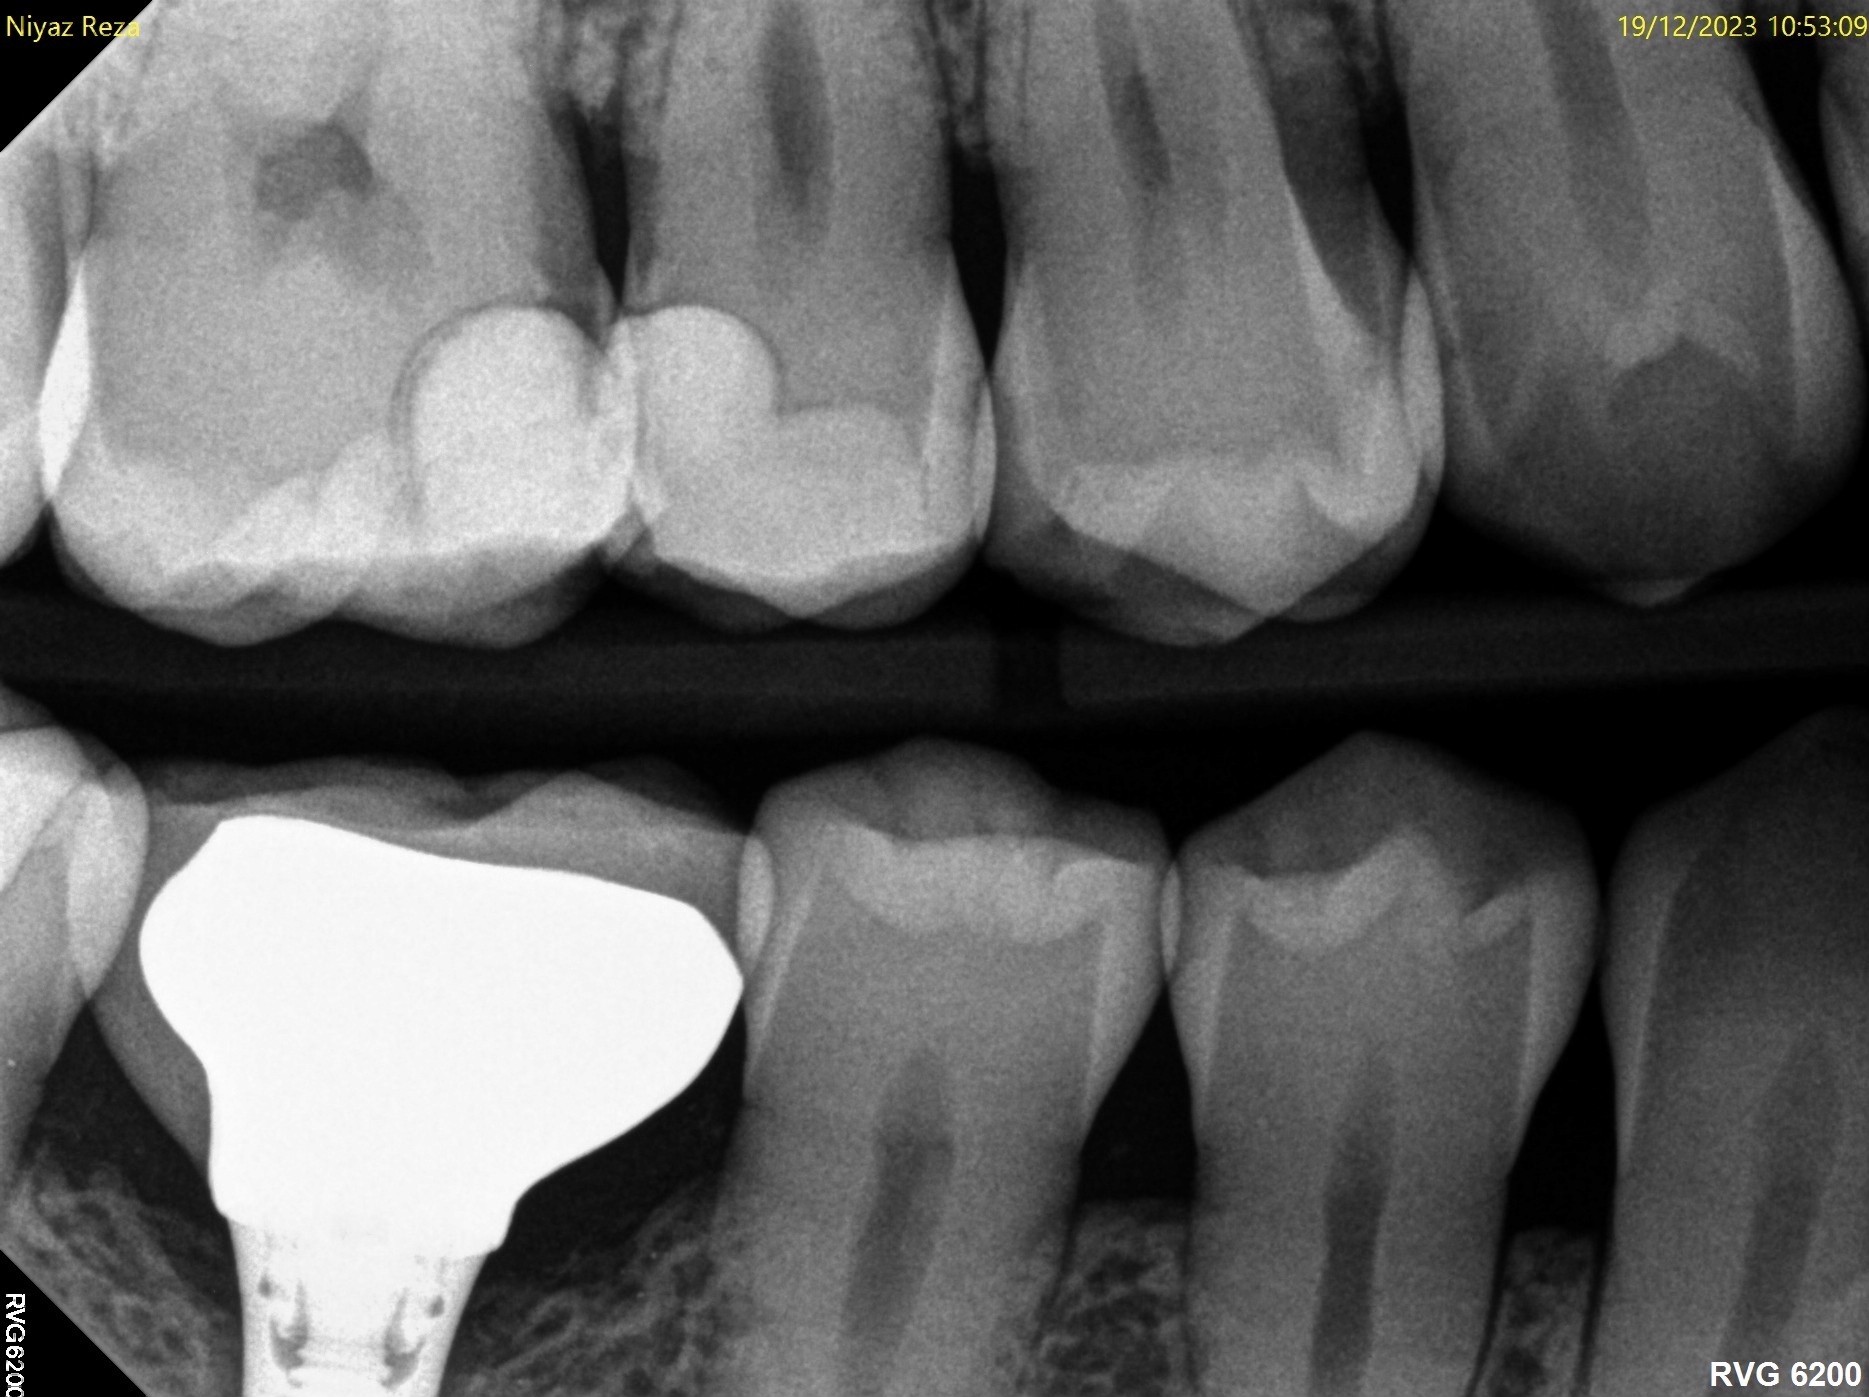

31. What option can be selected for the crown over the teeth # 2.4 and 2.5?